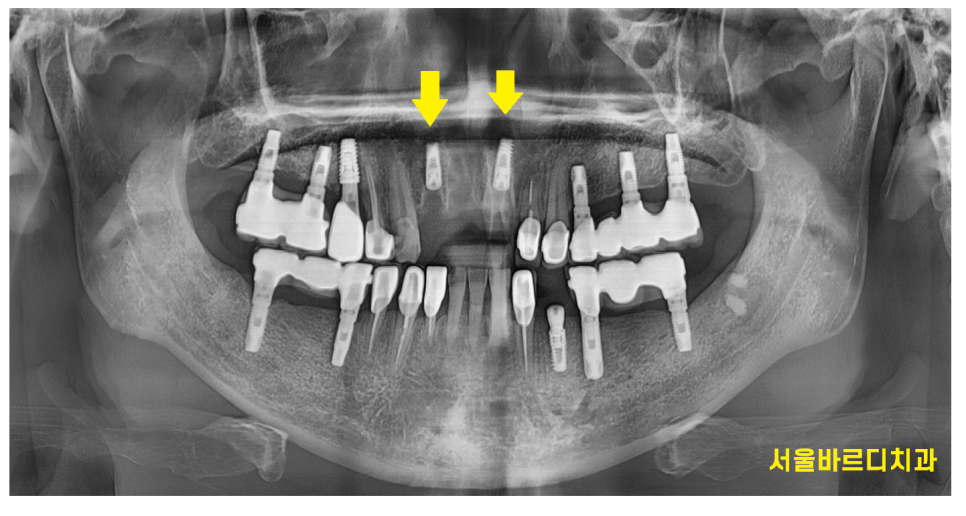

거의 뿌리만 남은 치아를 발치하고

상일동역 치과에서 임플란트 수술을 시행하였습니다.

치료 기간동안 사회생활은 하셔야하니

임시로 쓸 수 있는 틀니를 제작해드렸습니다.